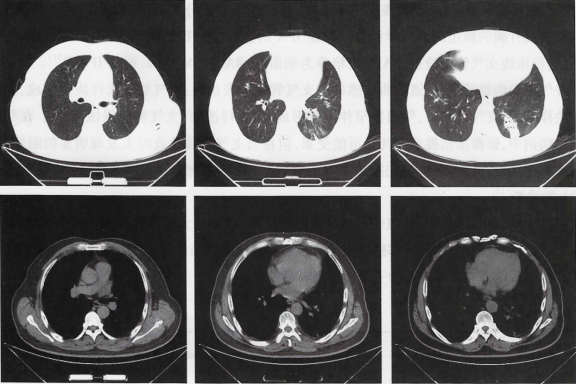

入院后第5天复查胸部CT示左下肺炎症及左侧胸腔积液较前好转。入院后第6天检验科口头报告BALF培养提示曲霉。患者仍觉胸闷气促明显,不能平卧,要求转上级医院继续治疗,遂转至浙江省第一医院,细菌及真菌培养发现大量烟曲霉及阴沟肠杆菌。予伏立康唑抗真菌治疗1个半月左右后至我院复查,自觉胸闷气急等症状较前明显改善,无发热,无咳嗽咳痰,无咯血等不适。复查胸部CT提示肺部阴影较前大部分吸收(图2)

图2  治疗后复查胸部CT